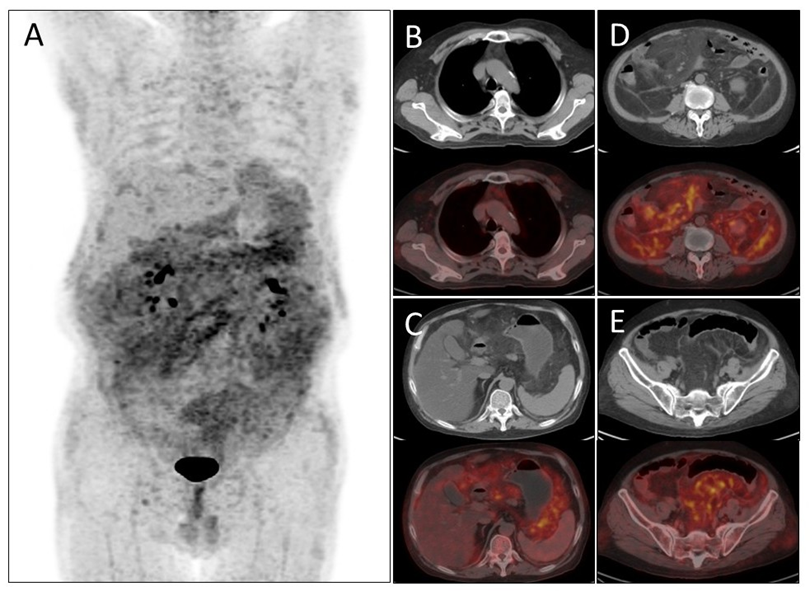

病例(3为一中年男性,因间断发热就诊;实验室检查示白细胞介素6水平升高;胸、腹部CT示右肺下叶斑片状实变灶,胸壁皮下脂肪密度增高,纵隔及腹腔脂肪密度增高;18F-FDG PET/CT示躯干部皮下脂肪、纵隔及腹盆腔内脂肪密度不均匀增高伴代谢增高;患者行腹腔内病变组织活检,病理示慢性脂膜炎(Panniculitis)。脂膜炎是一种累及脂肪组织的异质性炎症性疾病,其病因包括创伤、感染、肿瘤、药物损伤、免疫缺陷或脂代谢异常等;发病年龄以30-50岁为主;其临床表现多样、缺乏特异性,常表现为四肢和腹部无痛性、大小不等的皮下结节,可累及肠系膜、网膜、腹膜后脂肪组织、骨髓、肺、心肌、肝、脾、肾等内脏器官,并出现相应症状。实验室检查可有血沉增快及C反应蛋白升高;组织病理学表现分为急性炎症期、吞噬期及纤维化期。根据炎症细胞浸润部位的不同,可将脂膜炎分为间隔性脂膜炎(累及小叶间隔结缔组织)、小叶性脂膜炎(累及脂肪小叶)及混合型脂膜炎(同时累及间隔与小叶)三型。CT影像中,脂膜炎常表现为脂肪密度的增高,部分呈片状或包块影,增强扫描强化不明显;MRI一般呈T1WI低信号、T2WI高信号及压脂T2WI高信号;18F-FDG PET/CT可用于脂膜炎的诊断及其与恶性肿瘤、感染性疾病及风湿免疫系统疾病的鉴别诊断,病灶多呈轻-中度代谢增高。